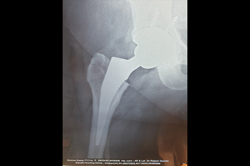

Neck Femur Fracture